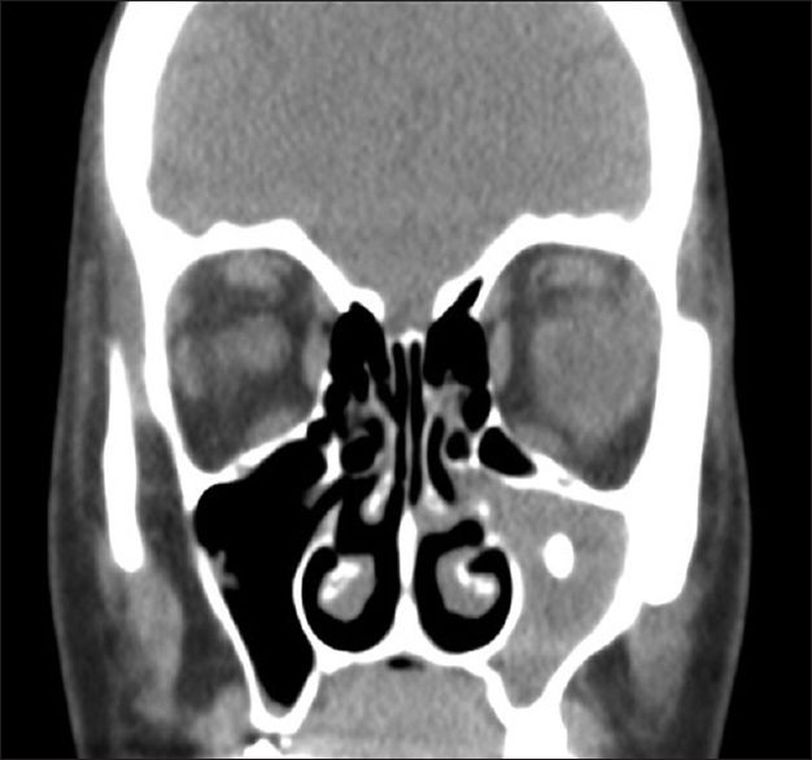

A 35 year old female presented to OPD with a complaint of recurrent nasal obstruction for the past 18 months. The nasal obstruction was more frequent in left side as compared to right side. Bilateral frontal headache along with loss of sensation of smell was also reported. On examination, there was bilateral inferior turbinates hypertrophy. However, anterior septal deviation towards left side with no polyps or discharge was also seen. The patient underwent routine pre-operative assessment. A paranasal sinuses CT was also performed which revealed a soft tissue radiodense mass in left maxillary sinus. A suspicion of foreign body in the floor of maxillary sinus was made. Functional Endoscopic Sinus Surgery (FESS) was planned and the foreign body was removed by suction. However, during exploration an object which looked like an entrapped tooth with no attachement to sinus walls, was seen. The object was extracted and sent for histopathology, which revealed it to have the exact consistency of a tooth. There were no post-procedure complications seen and the patient was discharged the very next day. Ref: Alwabili M, Aloulah M, Alsuwaidan R, Altuwaijri A. Tooth in maxillary sinus, less than what commonly anticipated. Saudi J Otorhinolaryngol Head Neck Surg [serial online] 2019 [cited 2020 Nov 18];21:52-4. Available from: https://www.sjohns.org/text.asp?2019/21/2/52/269715